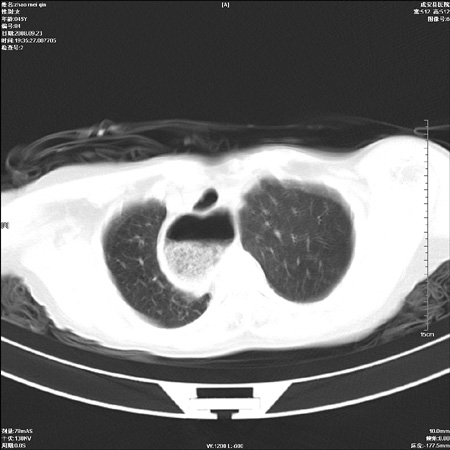

标题: CT15861:女 60 外伤后1小时 胸疼 [打印本页]

标题: CT15861:女 60 外伤后1小时 胸疼

外伤后1小时 胸疼 是外伤后引起的吗?

食道扩张明显下端逐渐变窄,倒像贲门失迟缓

食道ca术后胸腔胃,右肺挫伤?

非外伤性改变,典型的贲门失迟缓症

食道扩张明显下端逐渐变窄,大量食物存留,象贲门失迟缓症。